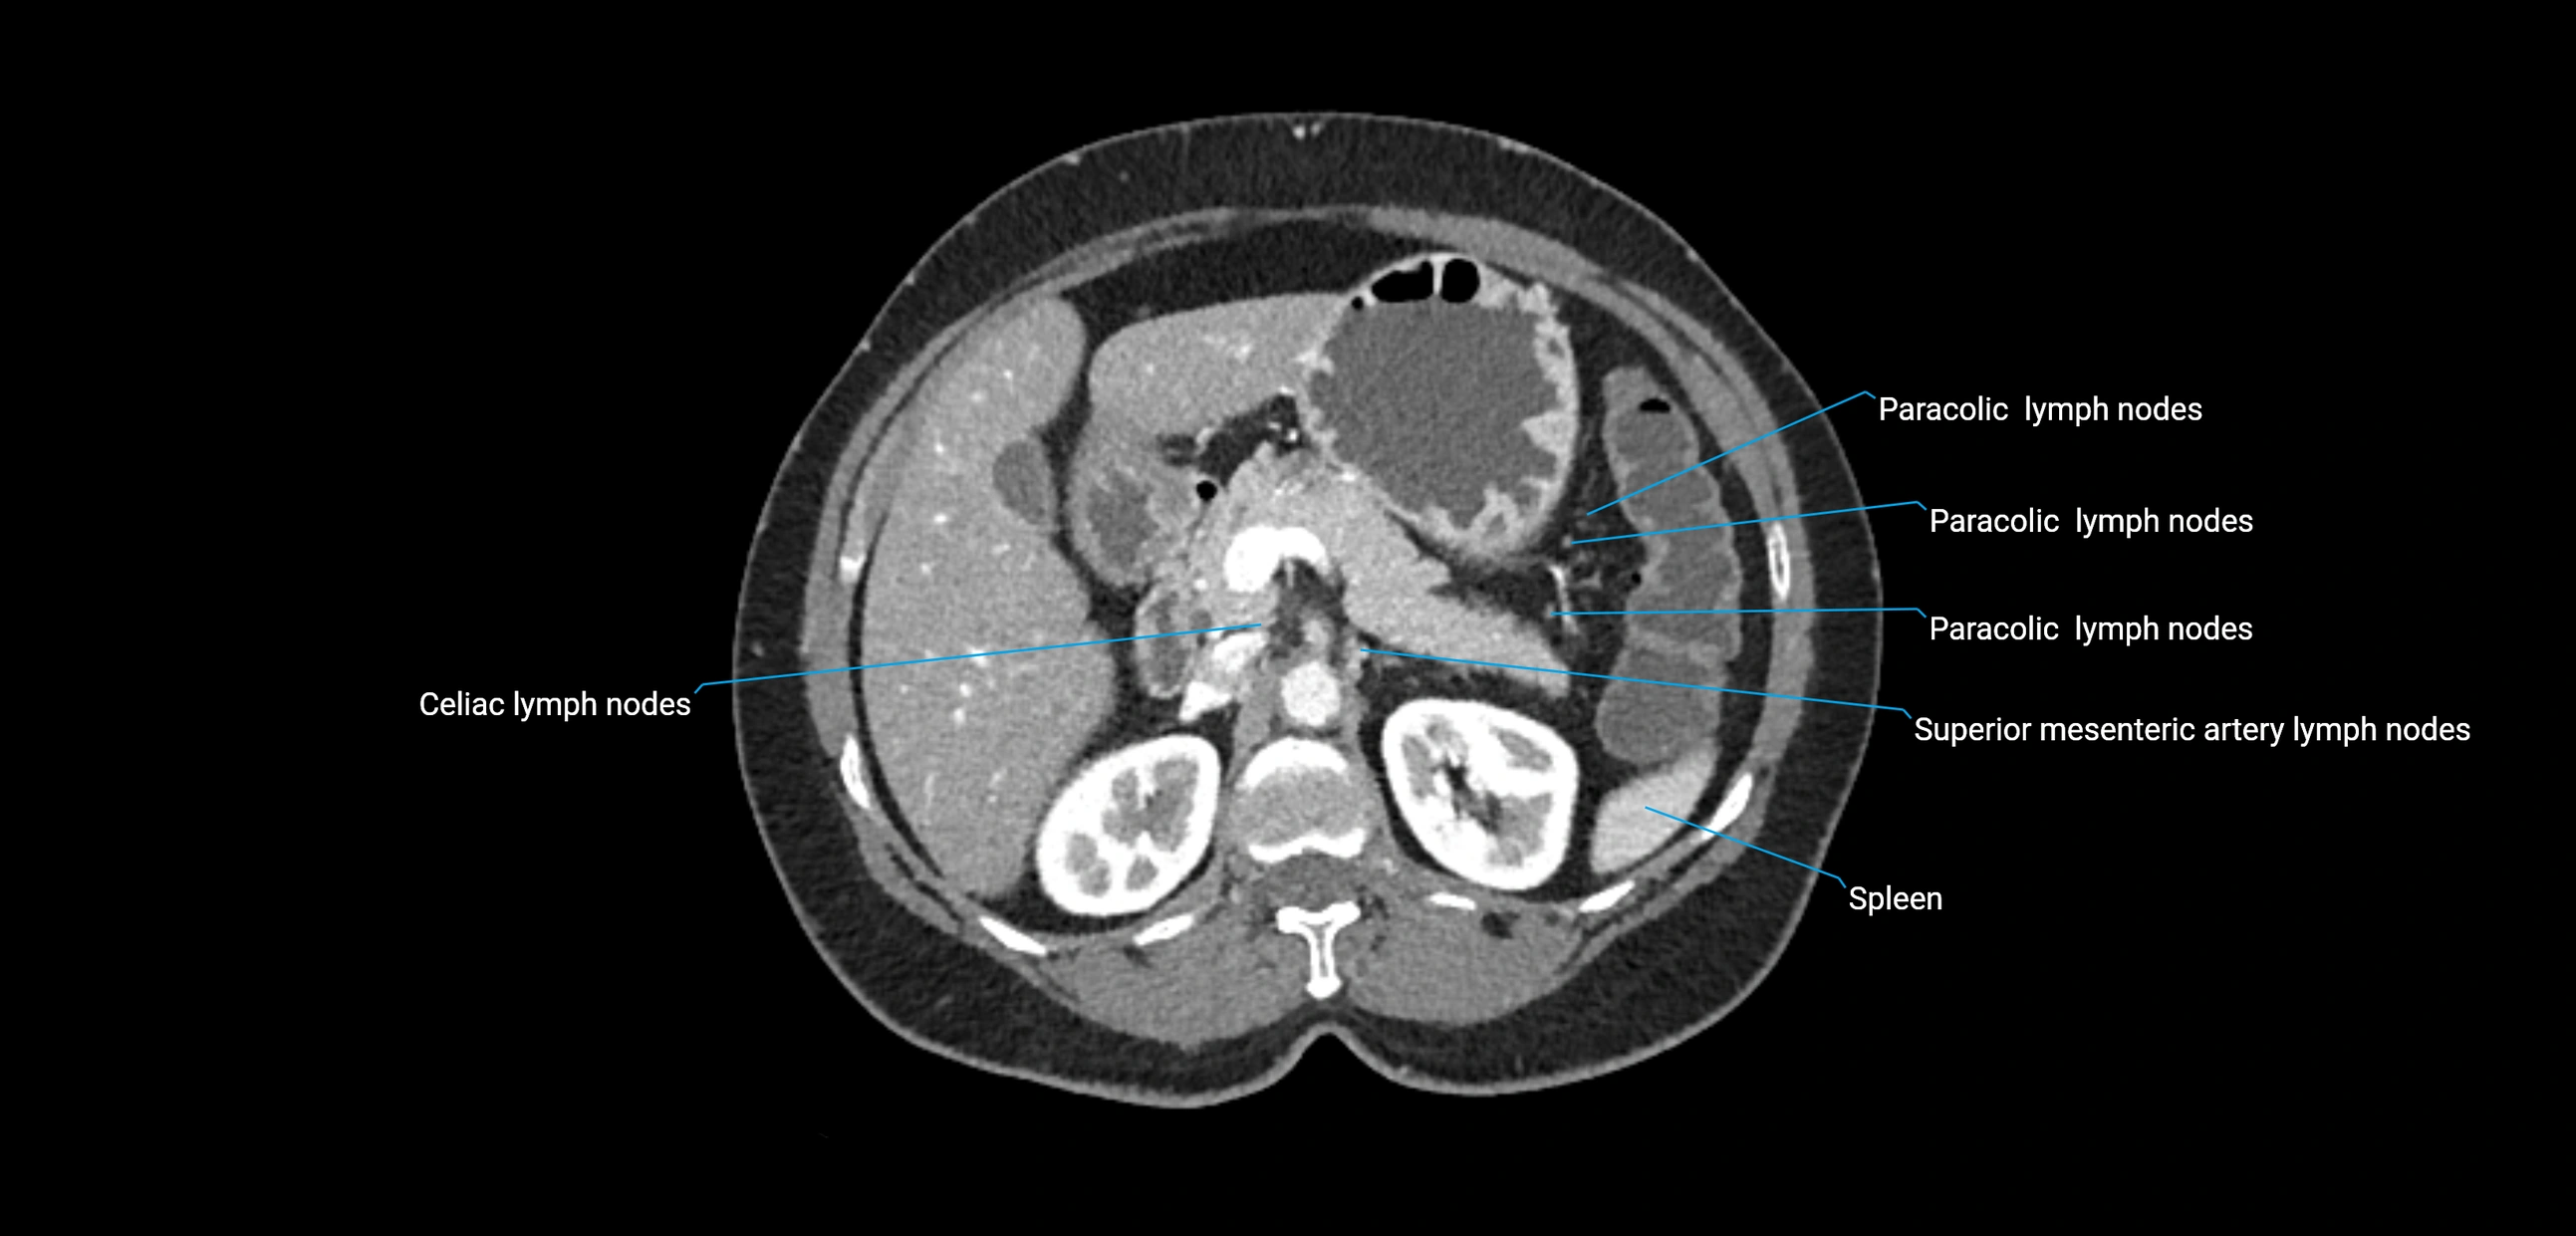

CT image

image